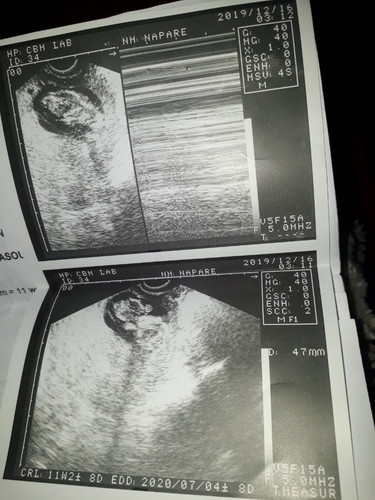

I am pregnant with 11weeks and 2 days today.

I have also a minimal subchorionic hemorrhage.. Sad to say.. I lost my baby at this time. the heartbeat is not detected anymore.. what will happen to me next? I don't have spotting or either bleeding or any vaginal discharge..

Eto po yung akin blighted ovum den kagabi lang lumabas 12/21/19 11weeks 2days din po ako. Ang tinake ko lang evening prim rose at buscopan

Hindi po ako nag pa raspa kusa po sya lumabas